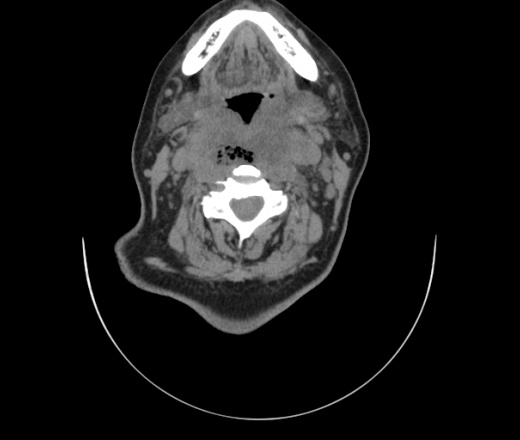

Женщина поступила в х/о спустя 4 дня после того как при употреблении карася подавилась костью.

Наличие газа в средостении на протяжении тел С2-С6 (медиастинальна эмфизема); рыбная кость на уровне тела С6.

При всем уважении, но говорить о медиастинальной эмфиземе, оценивая мягкие ткани шеи, как-то слишком резко. На мой взгляд, это ретрофарингеальное пространство.

Эвакуировали почти 100мл гноя. Но кость не смогли найти. Думаю что она даст дальнейшее ослоднение. Эндоскопически за черпалонадгортаной звязкой не смогли зайти в пищевод, все мягкие ткани отечные, просвет пищевода сдавлен. По всей видимости параэзофагеальная клетчака тоже задействована. Эмпиема, если ее можно так назвать, незнаю как правильно дошла до уровня яремной вырезки. Чем закончиться напишу. Ждем медиастинита.

Флегмона заглоточного пространства шеи, только операция, флегмоны вскрывают. Риск медиастинита.

Согласен с Вами; конечно, наличие газа в клетчатке ретрофарингеального пространства (затмение с опечаткой..). К сожалению, процесс "продвигается" к медиастиниту. Но почему никто, не отмечает наличие рыб. кости; или это для Всех очевидно?

Так вы уже отметили. Хотя ориентировал бы не скелетотопически, а на перстнечерпаловидный сустав.

Кость то мы сразу выявили, размеры где то 17*2мм, но ее так и не получается найти в этой каше